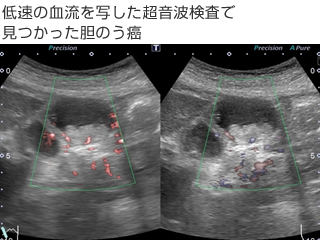

造影超音波検査は、卵アレルギーの患者さん以外で、CTやMRI 等の検査で造影剤を使うことが出来なかったアレルギーの方や、腎臓の働きが悪い方にも安全に行える検査法です。